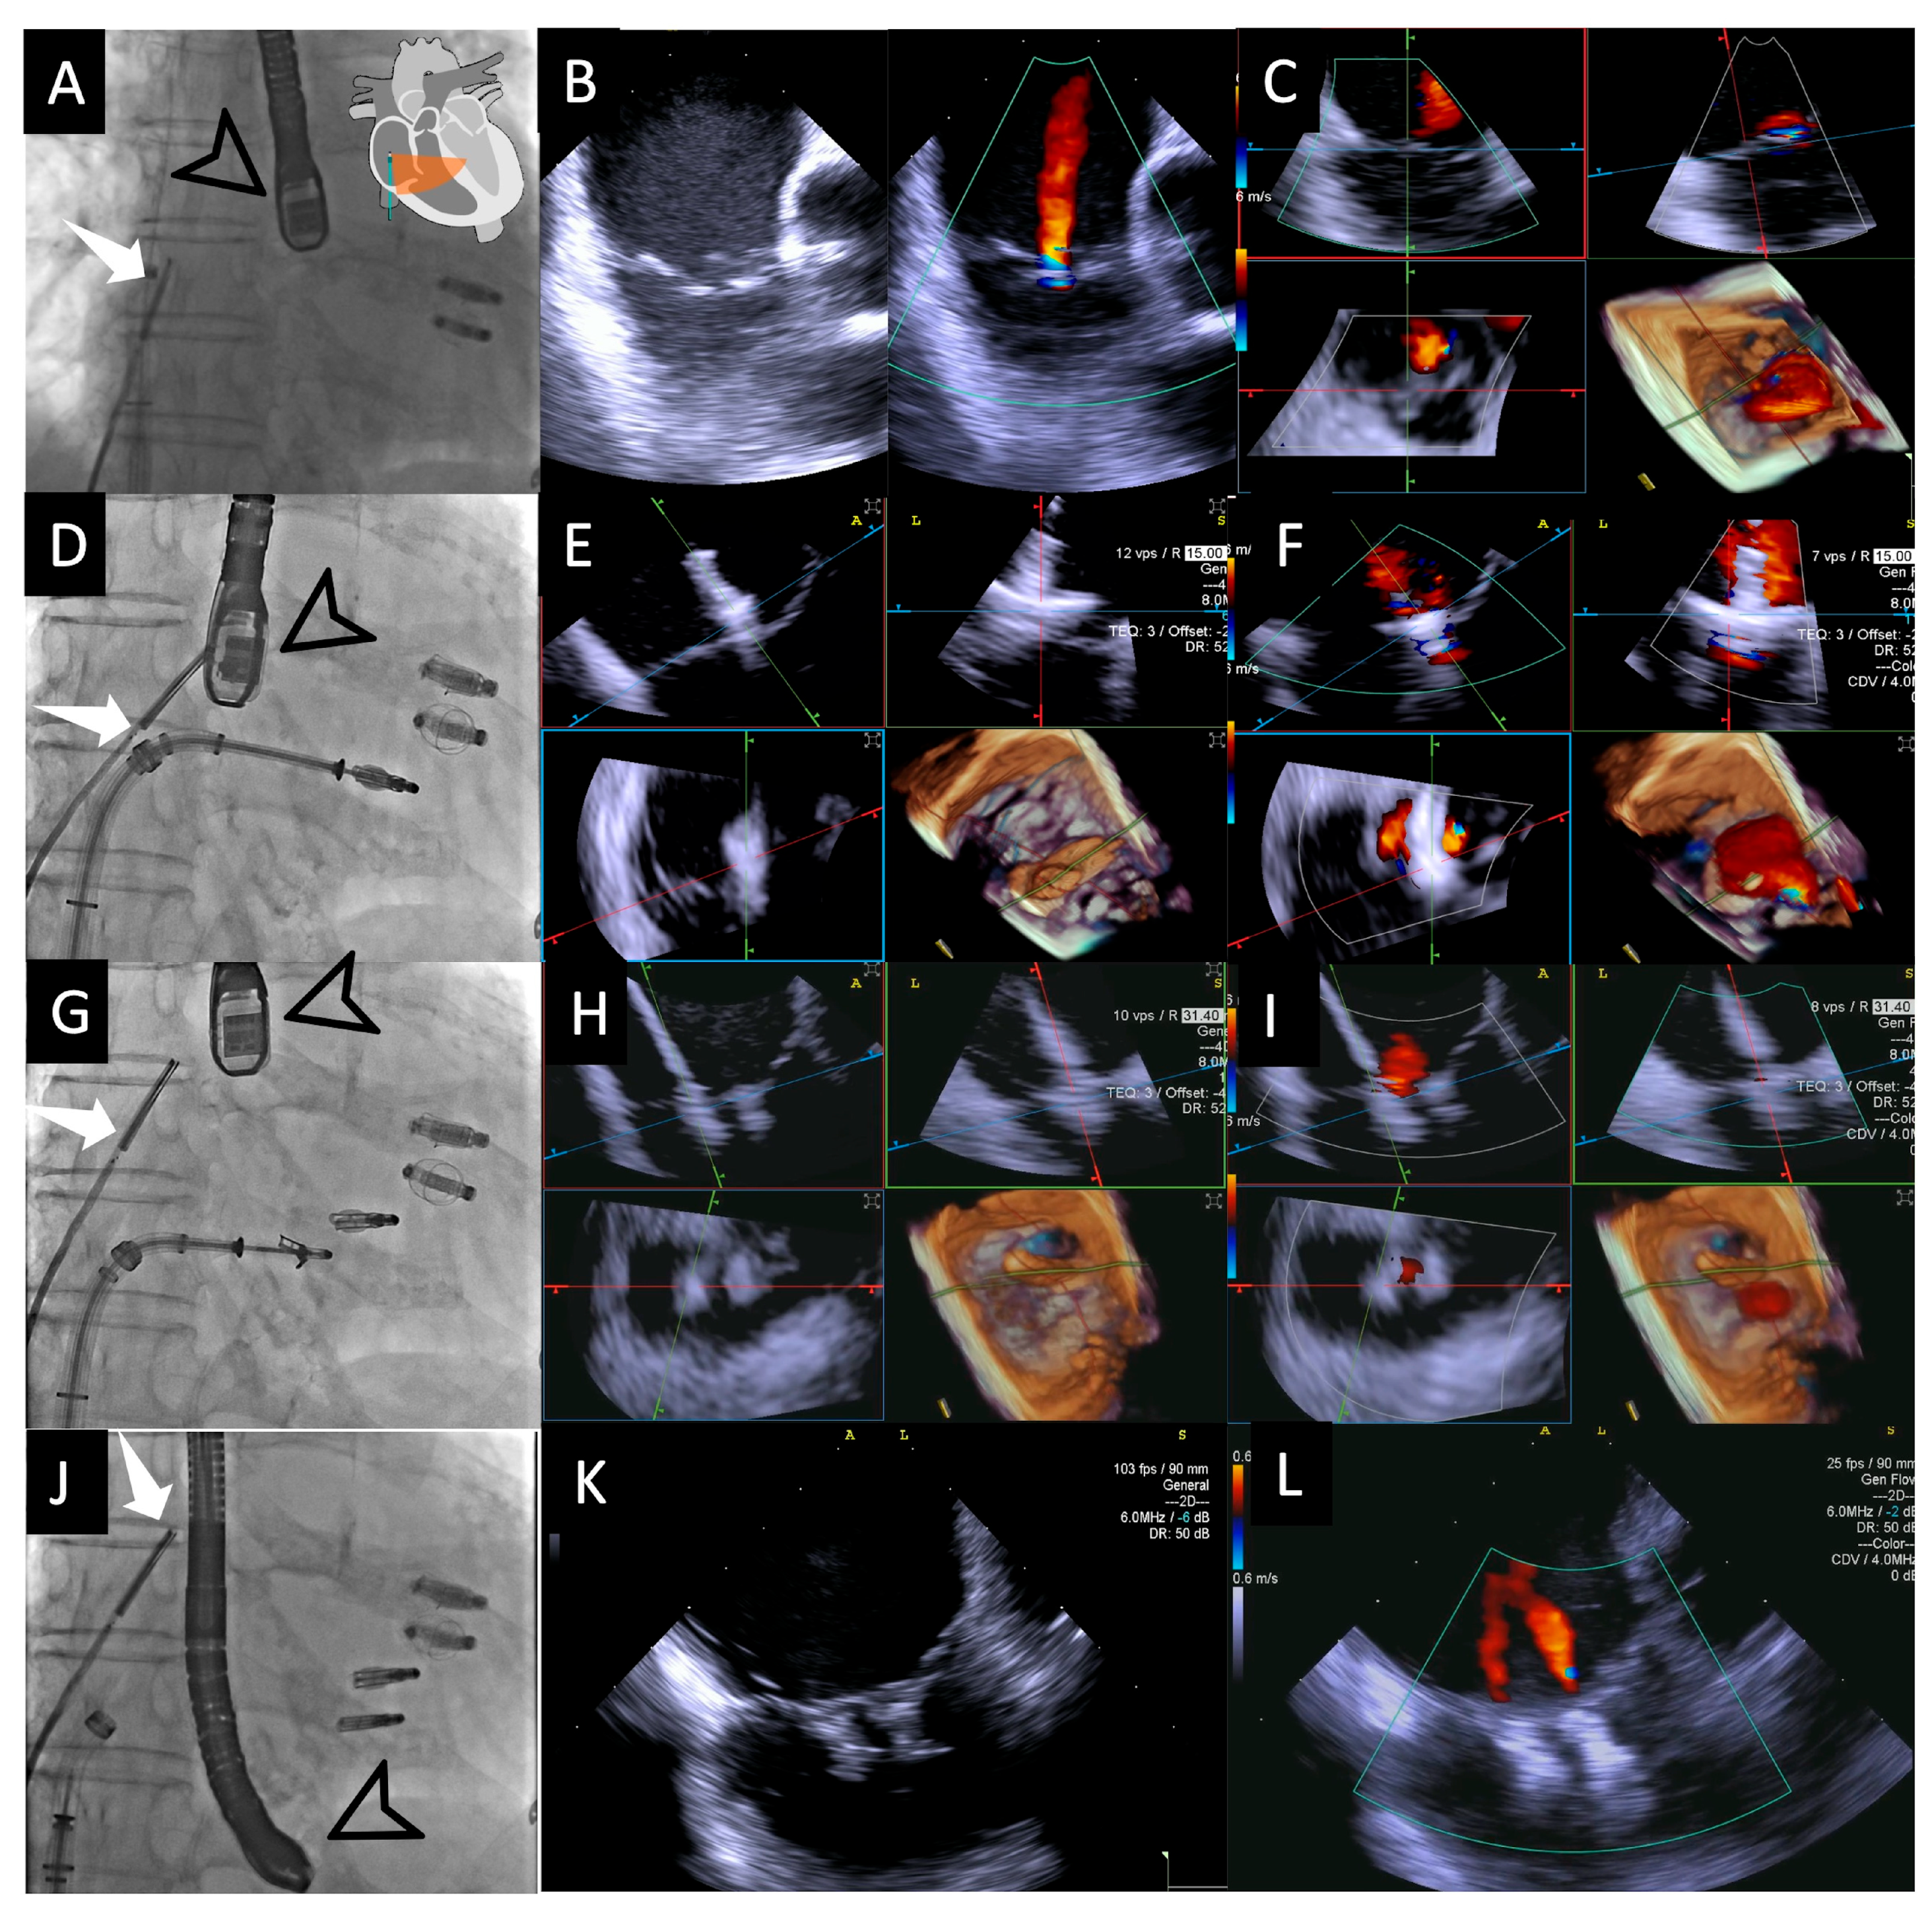

2.3. Procedural Steps

- Step number 1: assessment of tricuspid valve anatomy.

- Step number 2: identification of the target lesion.

- Step number 3: steering and valve approach.

- Step number 4: ensuring perpendicularity and correct trajectory.

- Step number 5: clocking.

- Step number 6: grasping.

- Step number 7: leaflet insertion.

- Step number 8: evaluation of residual regurgitant jets.